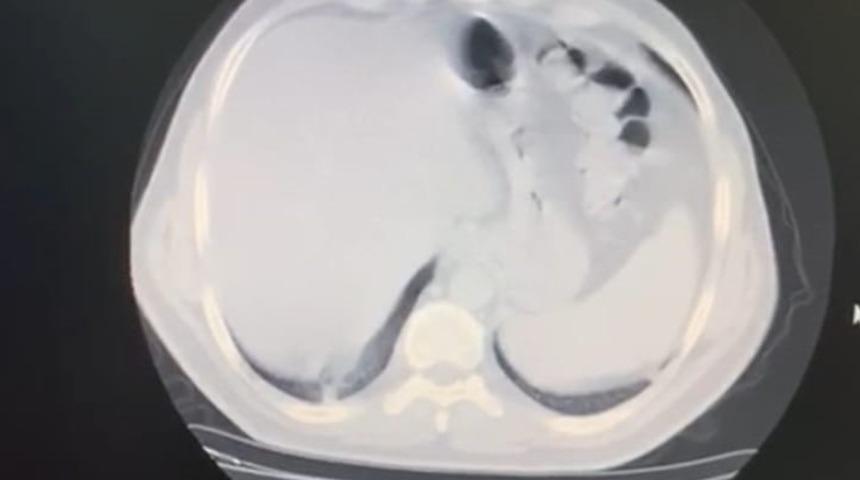

AKCİĞERİN YÜZDE 70’İNDE TUTULMA GÖRÜLDÜ

Evdeki 8 günlük sürecin ardından durumu ağırlaşan Civil, ikinci kez çekilen tomografide akciğerinde yaygın bir koronavirüs zatürre tutulumu görüldüğüne dikkat çekerek şunları söyledi; “Çok korkunç bir görüntü vardı. O görüntüyü görünce psikolojik olarak da çok etkilendim. Daha sonra hastaneye yatırıldım ve ateşim 41 derece civarındaydı. Oksijen satürasyonum da 70’lere kadar düştü. Yoğun bakım hastalarında kullanılan bir ilaca başlandı. Hastaneye yattığımın ilk 3 günü çok kritikti. Genel durumum bu 3 gün içerisinde yavaş yavaş bozulmaya başlamıştı. Nefes alamıyordum ve boğuluyordum. Sıkıntılı ve sancılı bir süreçti"

Tomografisinde görülen bulguların ne anlama geldiğini bildiği için ümitsizliğe kapıldığını ifade eden İstanbul Gelişim Üniversitesi Sağlık Bilimleri Yüksekokulu’ndan Dr. Öğretim Üyesi Celal Civil, “Vital bulgularım çok kötüydü. Acaba bu virüsü atlatamayacak mıyım? Yolun sonuna mı geldik? Buraya kadar mı? diye çok düşündüm. Klinik olarak kötü durumdaydım, radyolojik ve laboratuvar sonuçlarım da çok kötüydü. Nefes darlığı çok kötü bir duygu. Boğulma hissi yaşıyorsunuz. Boşuna nefes alıyormuş gibi hissediyorsunuz çünkü ciğerler koronavirüs tarafından tutulmuş durumda. Kafanızı suya sokup nefes almaya çalışmaya benziyor. Dakikada 8 litre oksijenle hayata tutunmaya çalışıyordum. 1 hafta boyunca oksijene bağımlı bir şekilde hastanede yattım. İlk günler dip yaşadım, hatta 2 kez yoğun bakım ekibi benim için geldi, entübasyon dahi düşünüldü” dedi.